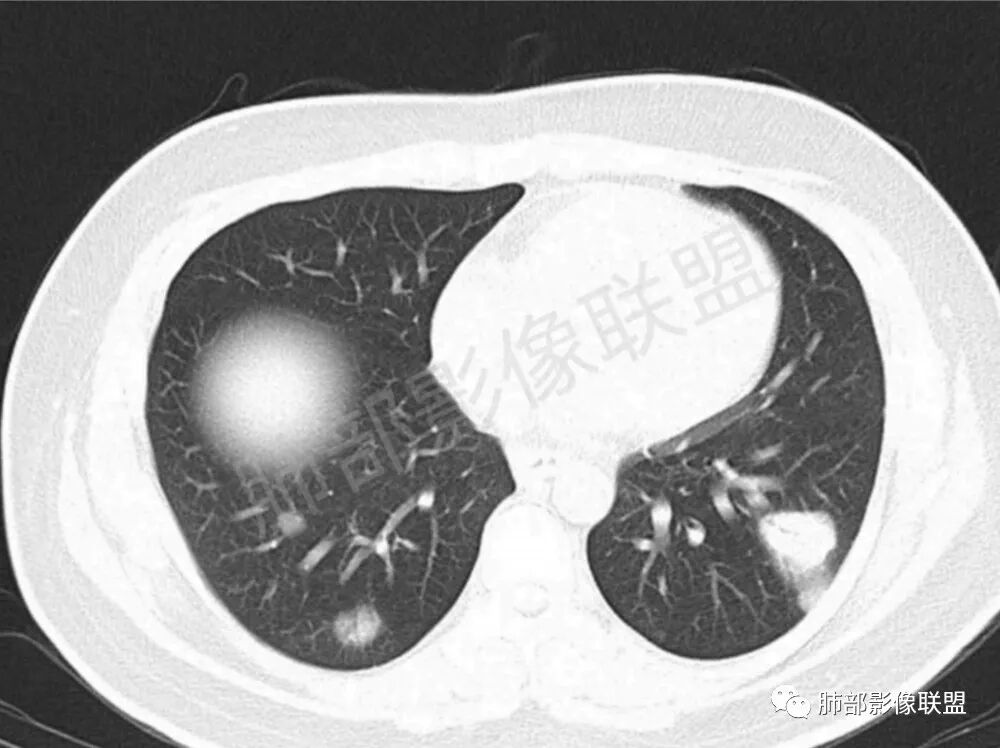

男性,22岁,HIV病史,症状半年,双肺多发大小不等结节影,边缘光滑,密度均匀,以胸膜下分布为主,部分与胸膜相连,胸膜下脂肪间隙可见,病灶近段支气管走行病灶内,远端似有堵塞,无增强图像,考虑隐球菌,鉴别:淋巴瘤,GPA

双肺多发结节影,膨隆,边缘光滑,圆顿,沿支气管血管束分布为主,部分贴胸膜,部分见空洞,空气支气管征

两肺多发结节性,大部分位于胸膜下,部分结节周围可见晕征。局部结节内可见扩张的支气管,纵隔淋巴结大,脾大,22岁男,HIV阳性,常规先考虑隐球菌。鉴别淋巴瘤,结核,马儿。

男,22,半年前咳嗽伴少痰,查HIV阳性,痰查TB阳性,既往有肺部斑片影伴空洞、纵隔淋巴结肿大、脾大。SCC、CA50、CA199、FER增高,此次胸部CT:两肺多发结节影,部分沿血管束分布,部分贴胸膜下,大小不一,密度不一,部分较散、边缘模糊,部分较实、圆钝、周围模糊晕,部分结节有支气管进入穿行自然,部分结节有血管分支自如通过。考虑HI∨相关淋巴增殖类病变,淋巴瘤?LYG?鉴别PC、TB。

1.双肺多发大小不一结节,外围为主,边界尚清,部分周围似有GGO

2.类圆形,部分与胸膜相连,糊墙

3.支气管通畅或近端堵塞

影像学缺乏特征性,以支气管血管周围、胸膜下及双肺下叶周边多发结节影最多见,结节易坏死形成空洞,伴有游走性和多变性的特征,结节周围可有磨玻璃样晕征,有时也可见单发结节影、薄壁的囊状阴影或弥漫性浸润影。肺门、纵隔淋巴结肿大少见, 可见胸腔积液和气胸。

肿块型∶表现为两肺多发大小不等的不规则肿块,肿块边缘不光整、欠锐利,有大的分叶,毛刺少见,增强扫描呈明显强化,可合并坏死、空洞;

结节型∶表现为两肺多发大小不等的结节,以两肺中下野多见,结节边缘欠锐利;